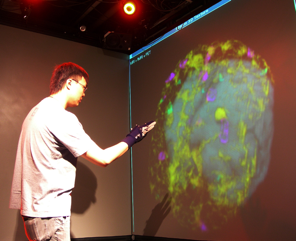

This project deals with the challenges of medical image visualization, in particular within the domain of neurosurgery. We wish to provide an effective means of visualizing and interacting with data of the patient's brain, in a manner that is natural to surgeons, for training, planning, and surgical tasks. This entails three fundamental objectives: advanced scientific visualization, robust recognition of an easily learned and usable set of input gestures for navigation and control, and real-time communication of the data between multiple participants to permit effective understanding and interpretation of the contents. The required expertise to accomplish these tasks spans the areas of neurosurgery, human-computer interaction, image processing, visualization, network communications.

Technologies that support manipulation in an efficient contact-free manner, coupled with visualization approaches that allow combination of multiple data sources, would significantly enhance the quality of information available during surgery. Moreover, the ability to share such visualizations at a distance while discussing them would offer tremendous opportunities for medical education in addition to expert training or peer coaching opportunities for complex procedures.

A major task is to implement the abstraction layer for rendering synthetic data, independent of display technology. This may involve use of the MNI's VTk-based IGNS system (IBIS) or build on our own rendering architecture, with low-level rendering engines for each display type, and input taken from existing neuro-visualization tools. In either case, the goal is to integrate the 3D rendering of MRI, fMRI, PET, DTI, and intra-operative ultrasound data, possibly in conjunction with the tracked position of surgical tools, and add modules for additional processing (e.g., feature highlighting, density control, and interactive manipulation/deformation). Rendering strategies must take into account the importance of merging volumetric and surface rendering techniques when dealing with the multiple data sets available.

Additional technologies will need to be integrated as the project advances, in particular, free-handed tracking (possibly wearing a surgical glove). Other possibilities being considered include projected overlay of data onto the patient's head in an augmented reality manner and combining "peel-away" visualization tools to allow the simulation of cutting away a layer of tissue in order to investigate what lies immediately below.

While improved display of volumetric brain data is likely to aid in understanding of the 3D content, little investigation appears to have been made into the question of how different display technologies and interaction paradigms affect perception and understanding of such data. To address this need, we are performing comparative studies of different display technologies (conventional 2D screen, head-mounted display, stereoscopic projection with polarizing filters, and autostereoscopic display) intended to evaluate their efficacy in communicating three-dimensional content, specifically, in the context of a neurosurgical planning task. While we hypothesize that stereographic display offers benefits over a monoscopic equivalent for understanding of volumetric content and their spatial relationships, our study is intended to quantify the differences in resulting task performance between these and against traditional monoscopic display. We conducted two experiments: virtual biopsy and volume carving.